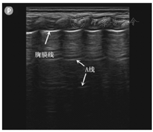

正常情况下,实时超声于胸膜线处可探及胸膜脏层与壁层随呼吸运动而产生相对滑动的征象,即肺滑动征。气胸时,胸腔内积气使肺和胸壁无法接触,表现为肺滑动征消失,而肺滑动征的存在即可排除气胸。既往已有文献报道,肺滑动征的消失诊断新生儿气胸的敏感性和特异性分别为95.3%和91.1%,阴性预测值为100%[17]。Liu等[18]最新研究表明,二维超声检查提示肺滑动征消失是诊断新生儿气胸最关键的征像,其敏感性为100%。然而,肺滑动征消失并非气胸的特异性表现,新生儿肺炎、肺不张等疾病也可出现此征象[19,20]。此外,若探头条件设置不当,也可能出现肺滑动征消失。因此,观察肺滑动征消失的同时,应根据BLUE程序进行下一步诊断[21]。

A线的产生是由于胸膜-肺界面高声阻抗差,产生多重反射而形成的水平伪像,表现为胸膜线下方平行于胸膜线、彼此间距相等的线性高回声。气胸情况下胸膜腔内出现气体,即可观察到胸膜线下出现密集的A线征。Liu等[18]对50例临床疑似气胸的新生儿进行床旁急诊肺超声检查,并进行胸部X线确诊,结果显示肺滑动征消失结合胸膜线和A线存在诊断气胸的敏感性和特异性均为100%。上述研究中,以胸部X线作为评估肺超声诊断新生儿气胸的标准,其100%的阳性预测值和阴性预测值还有待进一步的证实。Lichtenstein[22]以CT作为诊断气胸的标准,对200例ICU病例进行回顾性分析发现,肺滑动征消失结合胸膜线及A线存在诊断气胸的敏感性为95%,特异性为94%。